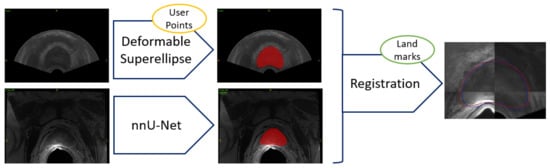

The workflow employed for achieving image fusion, starting with segmentation for both imaging modalities, namely TRUS and MRI, is reported in Figure 3. In the clinical practice, segmentation does not happen at the same time, since MRI segmentation can be achieved preoperatively, whereas the TRUS segmentation has to be obtained intraoperatively, at the start of the prostate biopsy procedure.

Figure 3.

Workflow for TRUS and MRI segmentation and subsequent image fusion. Segmentation from TRUS is achieved in a semiautomatic way by fitting a 3D model based on deformable superellipses starting from user-defined points in at least three slices. Segmentation from MRI is performed fully automatically by exploiting the nnU-Net framework. Registration can be either performed in an automatic way, or the user can add anatomical landmarks to constrain the space of transformations.

Then, having both segmentation masks from TRUS and MRI modalities, registration can be performed, enabling image fusion, which allows tissue coming from both modalities to be seen at the same time. Optionally, a set of anatomical landmarks can be inserted by the user to ease and constrain the registration optimization step. The procedure is presented in Section 2.5.